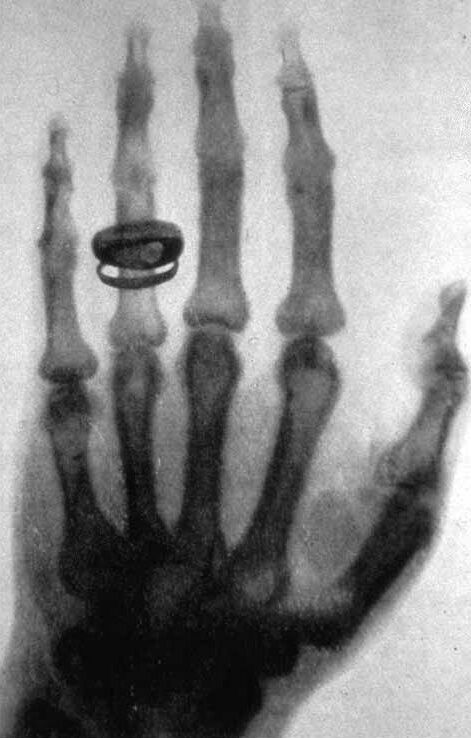

1870年にクントが再びクラウジウスの後任としてヴュルツブルク大学の教授になると、その助手となった。1872年にはチューリッヒ時代から交際して在学中に婚約していた6歳年上のアンナ・ラディッグと結婚している。アンナは後に、有名な右手のX線写真のモデルを務めている。同年クントがストラスブール大学に移ったため、これに帯同して引き続き助手となった。この頃からレントゲンは独立して実験を行なうようになる。

光のようなものは電磁波であり、この電磁波は陰極線のように磁気を受けても曲がらないことからレントゲンは放射線の存在を確信し、数学の未知数を表す「X」の文字を用いて仮の名前としてX線と命名した[9]。7週間の昼夜を通じた実験の末、同年12月28日には早くも"Über eine neue Art von Strahlen"(『新種の放射線について』)という論文をヴュルツブルク物理医学会会長に送っている。さらに翌1896年1月には、妻の薬指に指輪をはめて撮影したものや金属ケース入りの方位磁針など、数枚のX線写真を論文に添付して著名な物理学者に送付した。

2003年、『ライフ』誌は、レントゲンが初めて撮影したX線写真を「世界を変えた100枚の写真」の1枚に選んだ。